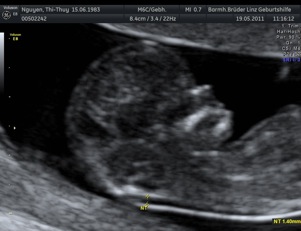

2. Organscreening idealerweise in der 22.-24. SSW - hier Termin vereinbaren!

Neben den ganz normalen MUKIPA-Untersuchungen liegt der Schwerpunkt der gynäkologischen Wahlarztpraxis in der Ultraschalldiagnostik,

d.h. pränataler Ultraschall (Messung der Nackendicke, Organscreening) einerseits, andererseits kann noch eine Untersuchung mittels 4D-Ultraschall durchgeführt werden,